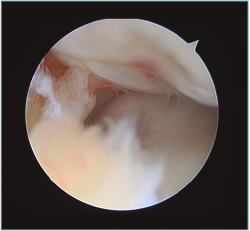

Pueden ampliarse los portales 1 cm a modo de mini-open para facilitar la extracción del fragmento libre articular o la fijación del mismo si fuera necesaria (Figura 7). Una vez extraído el cuerpo libre, se puede refrescar la zona origen del defecto con un sinoviotomo o incluso realizar unas perforaciones con un punzón o una aguja de Kirschner de 1,8-2 mm, con una separación entre ellas de 2-3 mm aproximadamente, para favorecer la creación de un tejido fibrocartilaginoso que proteja la zona (Figuras 8 y 9)(10). Por esta misma vía se pueden realizar técnicas complementarias como la introducción de matrices celulares o biogeles (véase más adelante).

Figura 9. Sangrado del hueso osteocondral tras perforaciones.